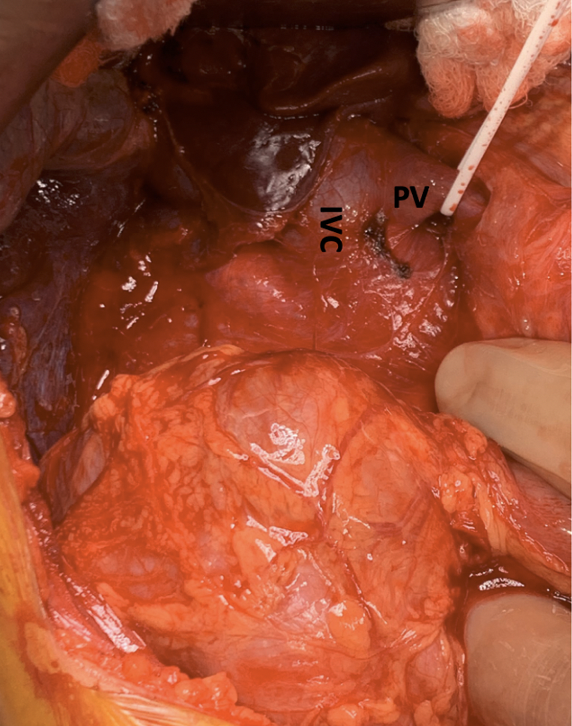

Case report: A 8-year old female child who was diagnosed with CAPV was referred to our centre for further evaluation. She was a full-term baby and doing well till 4years of age when she had near fainting. During evaluation she had elevated liver function test, splenomegaly and imaging revealed CAPV with shunting. Her family reported decline in her academic performance over past few years. On index visit her total bilirubin was 1.4 mg/dL, AST 40 IU/L, ALT 29 IU/L and serum ammonia 122 ug/dL with no evidence of hepatopulmonary syndrome. The CECT abdomen revealed common trunk of splenic vein and SMV, directly draining into IVC with prominent hepatic artery (Figure 1). She received deceased donor liver transplant from brain dead donor (Figure 2) and postoperative course was uneventful. Liver function has remained stable with patent PV and hepatic artery. Histology of the native liver showed absent PV with nodular liver parenchyma without cirrhosis.